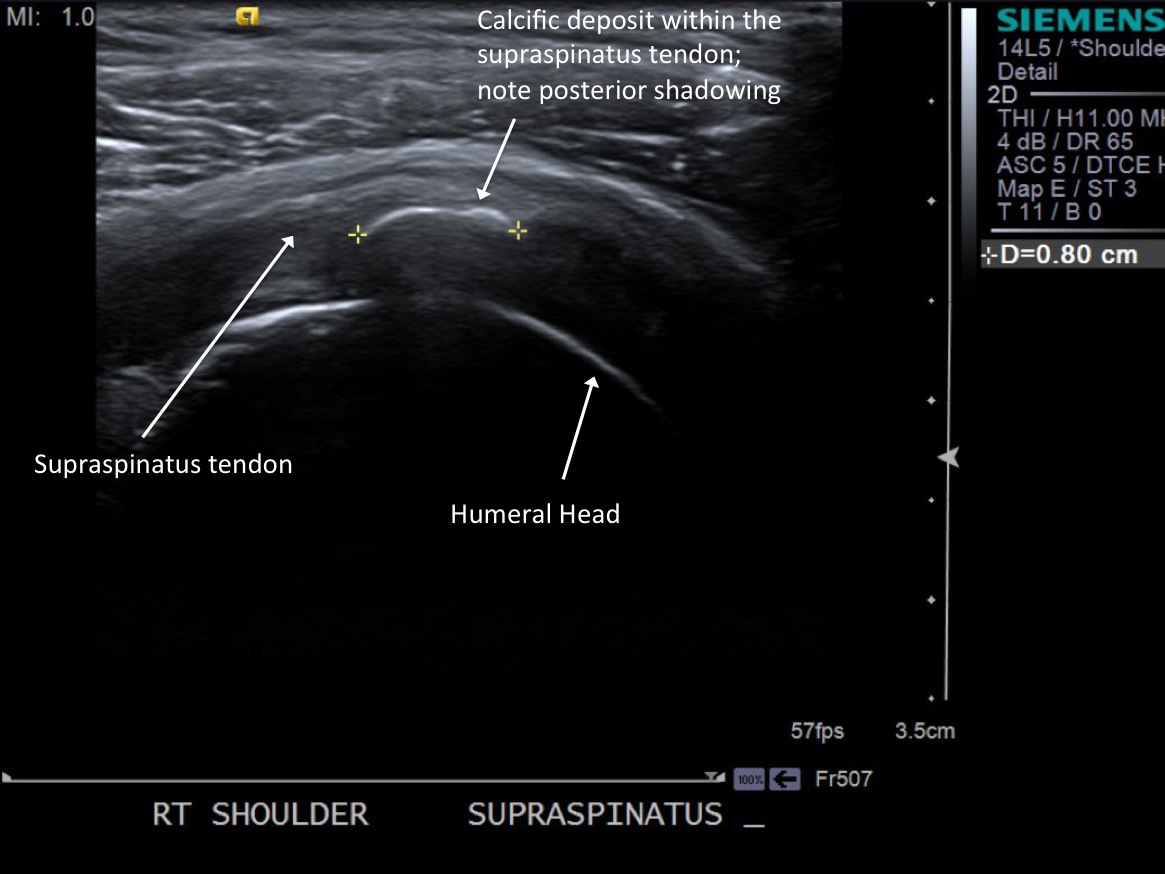

• descriptiondescription

Long axis view of supraspinatus tendon with calcific deposit

• Probe: 14Mhz or 9Mhz Linear

3.Scan patient looking for calcific tendinosis deposition typically in the supraspinatus tendon. Measure size of largest deposits.